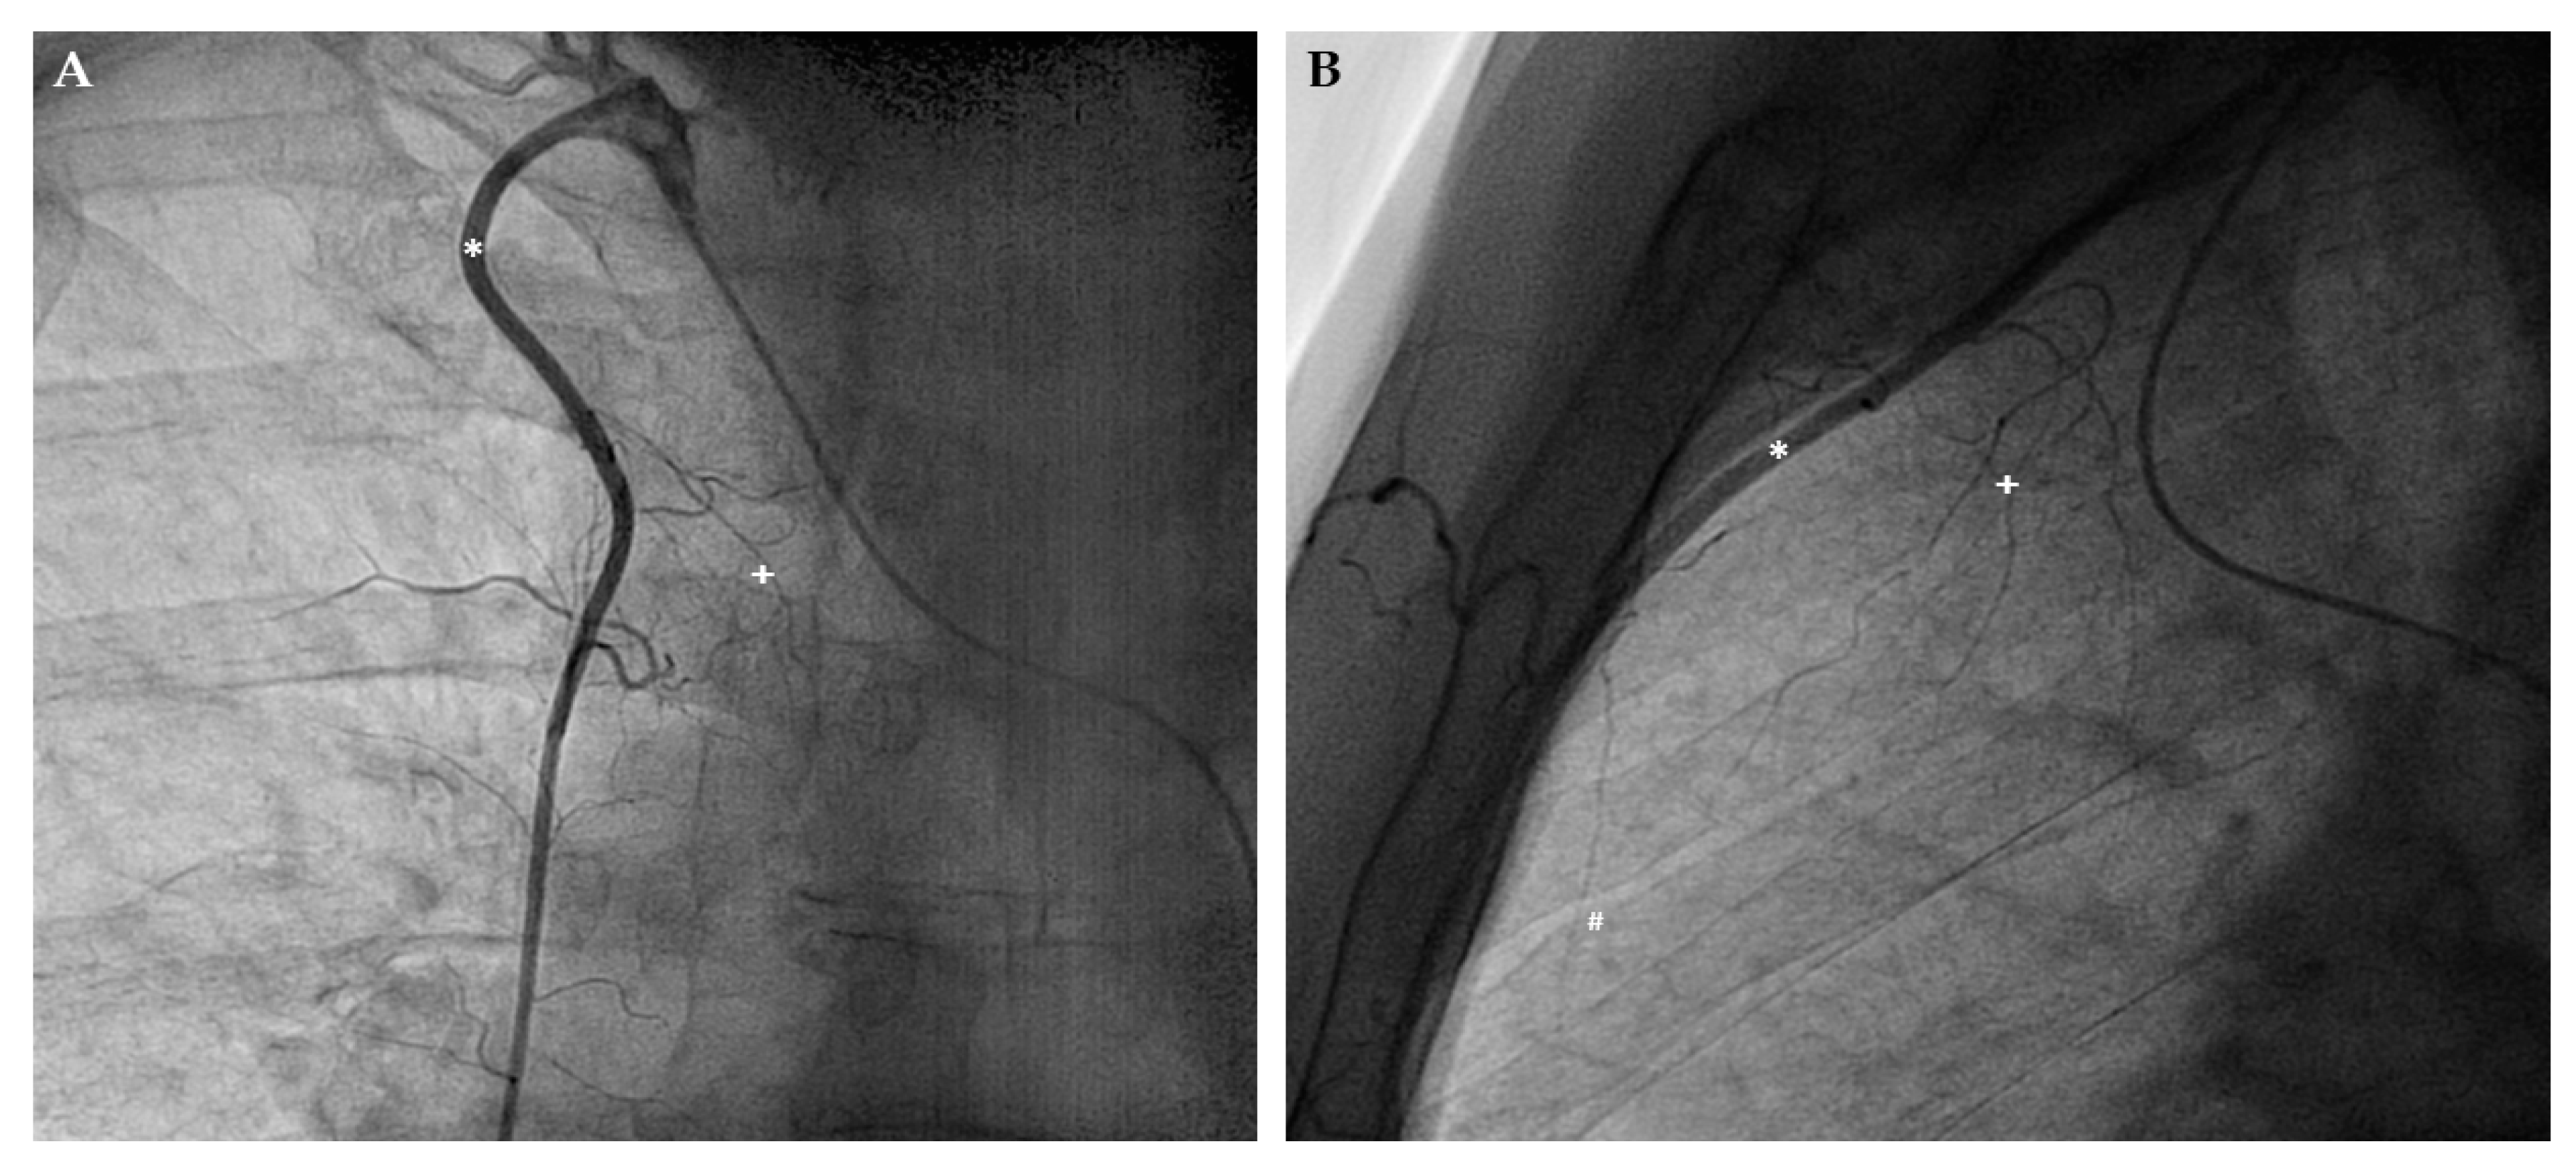

- Stoller, M.; de Marchi, S.F.; Seiler, C. Function of natural internal mammary-to-coronary artery bypasses and its effect on myocardial ischemia. Circulation 2014, 129, 2645–2652. [Google Scholar] [CrossRef]

- Stoller, M.; Seiler, C. Effect of Permanent Right Internal Mammary Artery Closure on Coronary Collateral Function and Myocardial Ischemia. Circ. Cardiovasc. Interv. 2017, 10, e004990. [Google Scholar] [CrossRef]